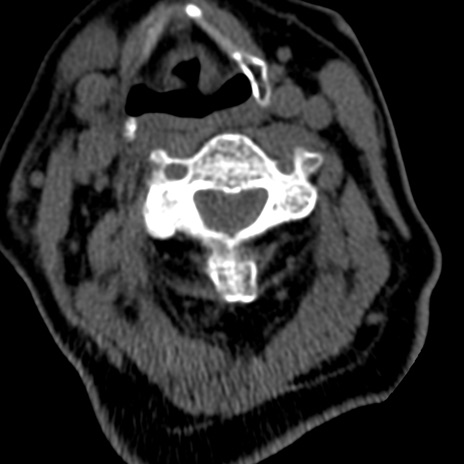

症例50 頚椎CT(横断像)

矢状断像